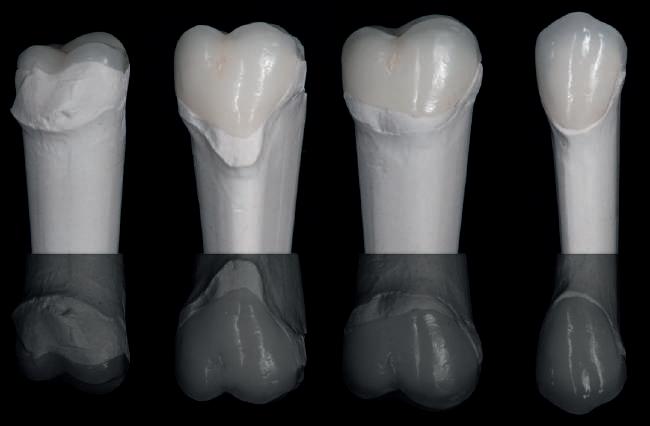

Cazul (1): Reprepararea intraorală a bonturilor Figurile

1. Aspect după inserarea primului set de bonturi implantare individualizate.

2. După 7 luni, bonturile individualizate din prima etapă au prezentat recesie de 1-3mm.

3. Bonturile repreparate intraoral.

Alt caz (1) Figurile

4. După osteointegrarea implantului 2.4., s-a observat recesia în etapa de amprentare a implantului 2.5.; s-a decis reprepararea marginilor bontului individualizat CAD/CAM 2.4. Înainte de preparare s-a aplicat şnur de retracţie pentru a evita lezarea ţesutului şi a îmbunătăţi vizibilitatea dintelui 2.3. şi a marginii bontului implantar individualizat. Aşa cum era de aşteptat, recesia a fost mai mare de-a lungul versantului distal al bontului 2.4. adiacent locului de extracţie vindecat/cu implantul mai nou.

5. Bontul individualizat aplicat (2.5.) cu bontul repreparat anterior (2.4.). Nu a survenit recesie nouă de o perioadă de peste 3 ani.